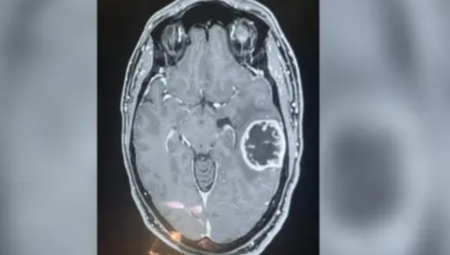

طور فريق بحثي بريطاني اختبارًا جينيًا جديدًا يمكنه تشخيص أنواع أورام الدماغ خلال ساعات بدلاً من أسابيع، مما يعد خطوة كبيرة نحو تحس ...